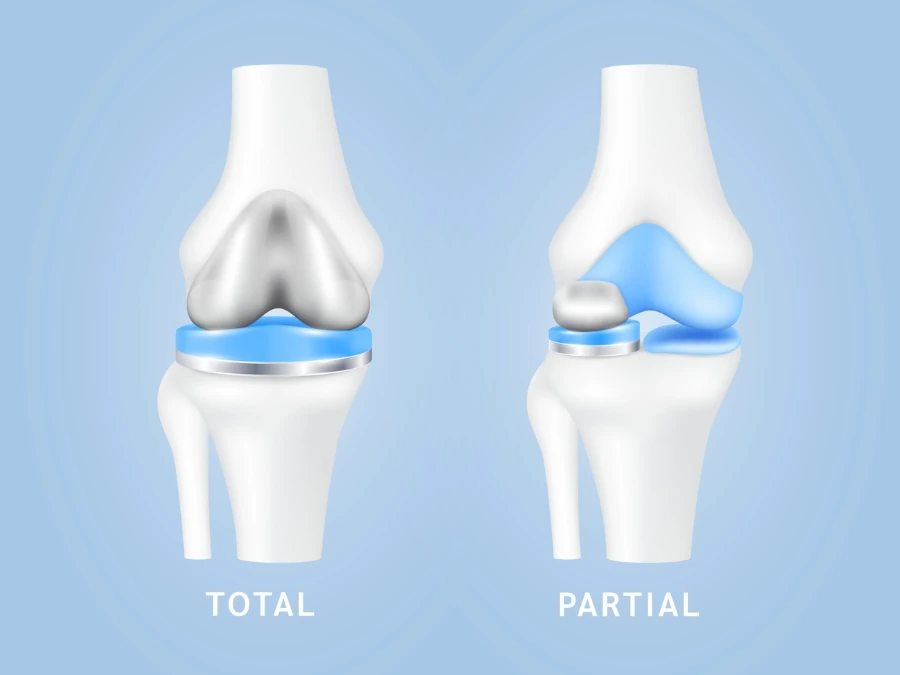

Le soluzioni protesiche disponibili

A seconda dell’estensione del danno, si può optare per una protesi totale o per una protesi parziale. La sostituzione totale viene eseguita quando tutte le componenti dell’articolazione sono coinvolte, mentre quella monocompartimentale è adatta solo in presenza di un’usura limitata a una sola porzione del ginocchio.

La scelta viene fatta in base a criteri precisi, valutando attentamente l’anatomia dell’articolazione e le condizioni dei legamenti, oltre alle caratteristiche del paziente in termini di età, stile di vita e grado di attività.